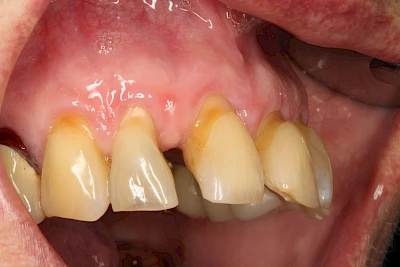

Keilförmiger Defekt

Eine Sonderform sind sogenannte keilförmige Defekte im Bereich der Zahnhälse. Hier geht man davon aus, dass Knirschen und Pressen in Kombination mit falschen Putzgewohnheiten (zu hoher Putzdruck, Verwendung von Zahnpasta mit hohen Abrasionswerten) eine Rolle spielen.